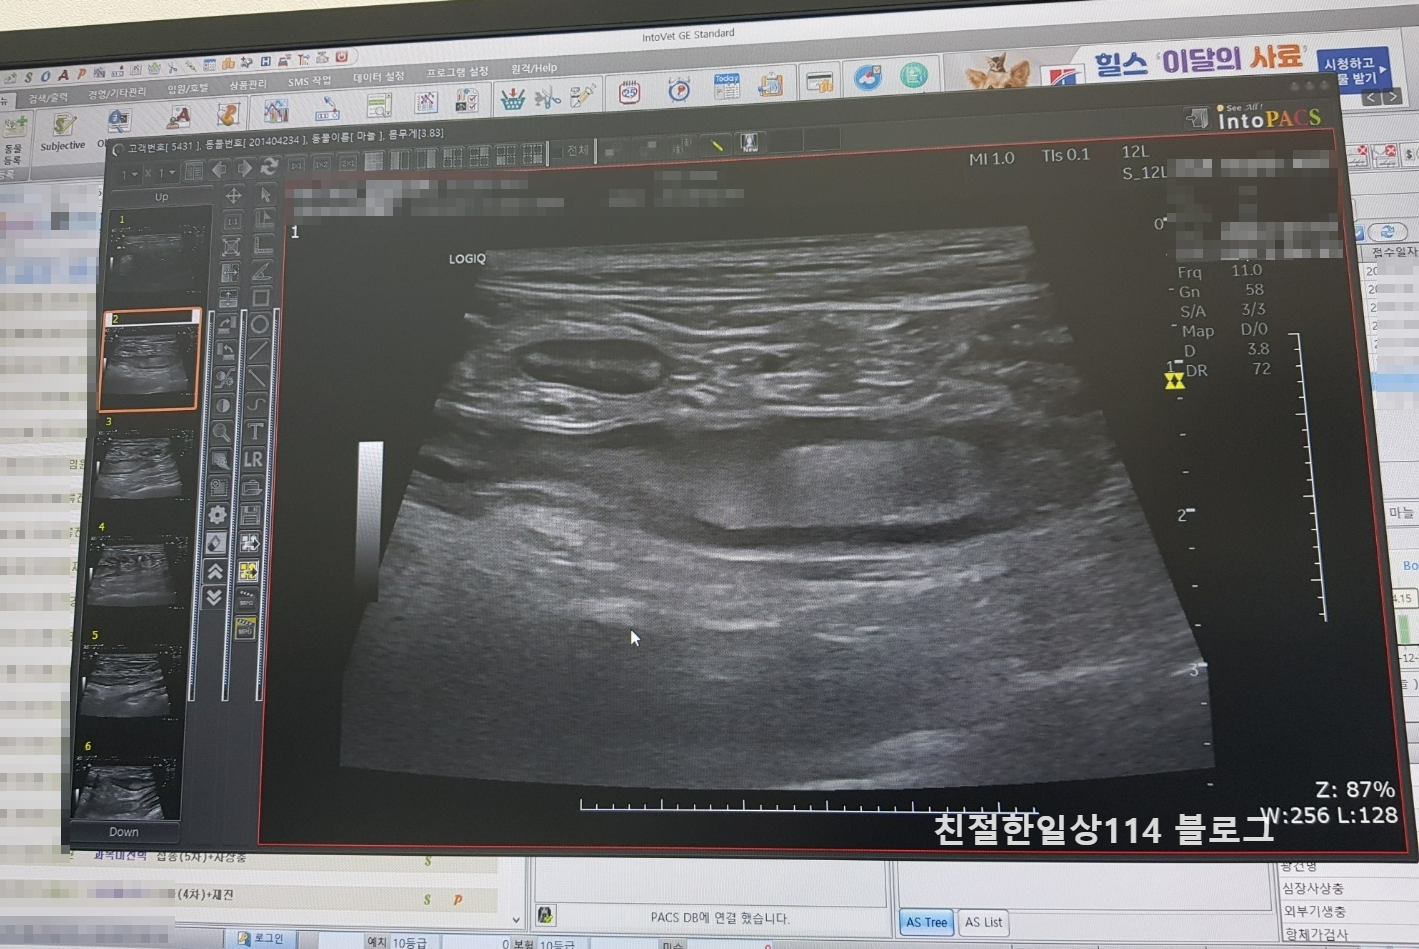

동물병원에서 수의사에게 상태를 설명하고 먼저 엑스레이 촬영을 해보았다. 엑스레이 촬영 사진을 보니 위장에 가스가 차있는 것과 이물질들이 보였다. 엑스레이 검사만으로는 원인을 알기 어려웠다.

가스와 이물질이 어디를 막고 있는건지 좀 더 자세히 보기 위해서 추가로 복부 초음파 검사와 채혈검사(혈액검사와 전해질 검사)를 함께 진행했다.

검사결과 위장 아래에 있는 십이지장과 소장이 심하게 구불구불하게 보여 급성장염으로 진단하였다. 정상의 장은 일직선으로 곧아야하지만 구불구불하다는건 염증이 생겨 경직되어있는 상태라고 설명을 들었다.